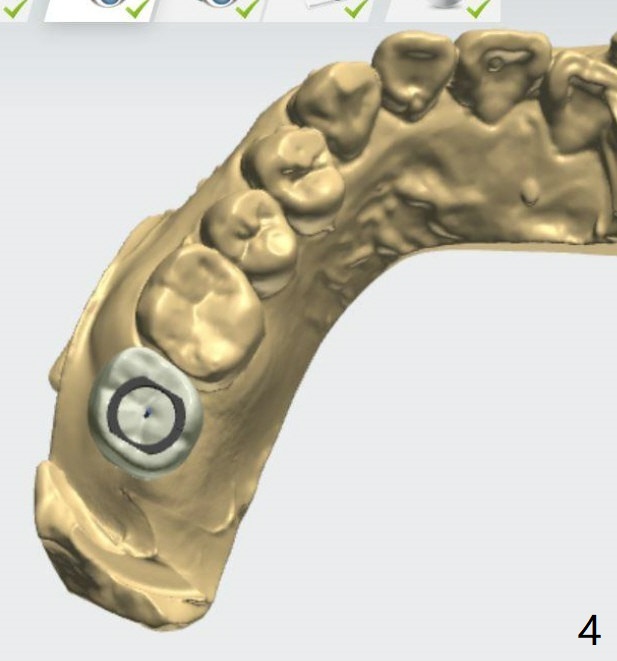

Implant Tilts Distal to Avoid 3rd Molar

A 40-year-old woman requests implant at #2 without removing the impacted 3rd molar (1 year 4 months post socket preservation). In order to do that, the implant should be tilted distal coronally. To reduce screw loosening, use UF implant.